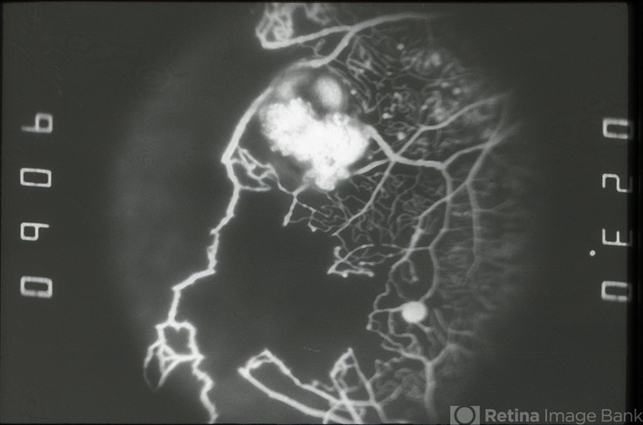

- VON HIPPEL

- Von Hippel-Lindau, fluorescein angiogram (FA)

- FA image of capillary non-perfusion and retinal angiomas of Von Hippel-Lindau OS.